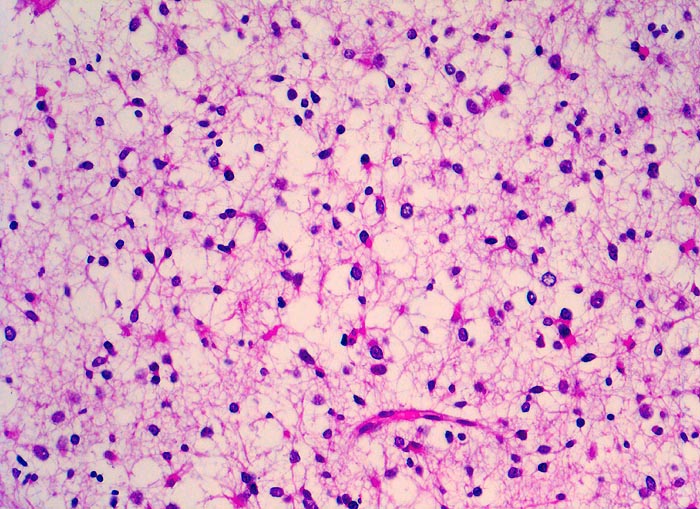

Histologisch bestehen die Oligodendrogliome aus kompakten Aggregaten runder Zellen mit deutlichen Zellgrenzen und klarem Zytoplasmasaum um einen dichten runden zentralen Kern (“Spiegelei”). Die Vakuolisierung des Zytoplasma stellt einen Fixationsartefakt dar und fällt bei Schnellschnitten als diagnostisches Hilfsmittel weg (Gefrierschnitt!). Charakteristisch sind verzweigte Kapillaren. Die Tumorzellen infiltrieren die Hirnrinde diffus und können sich bis in die Meningen ausbreiten.

• Fokale mukoide/zystische Degeneration innerhalb des Tumors mit Ausbildung von Pseudozysten.

• Dichtes Netzwerk verzweigender Kapillaren.

• Tumorzellen umgeben von einem Halo ("Spiegeleier").

• Die Tumorzellen erinnern an Oligodendrozyten der weissen Substanz, haben aber deutlich grössere Kerne.

• Im Gegensatz zum Glioblastoma multiforme monomorphes Zellbild.